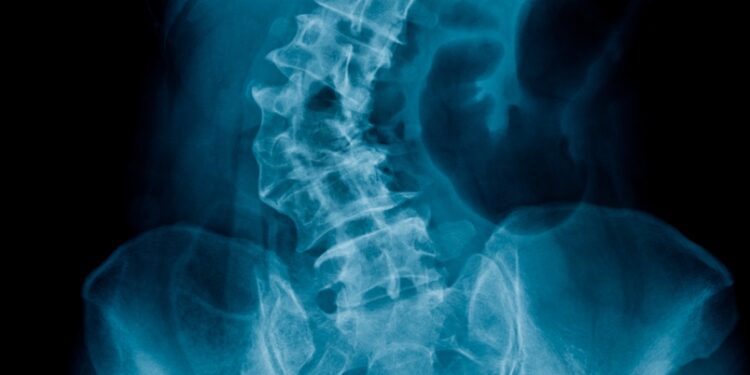

Esant reikalui, gydytojas gali paskirti papildomus tyrimus: rentgeno nuotraukas (dažniausiai iš priekio ir šono), kartais – magnetinio rezonanso arba kompiuterinės tomografijos tyrimus, kurie leidžia tiksliai įvertinti stuburo būklę.

Iškrypimo kampas matuojamas specialiu prietaisu – skoliometru, kuris uždedamas ant nugaros. Tikslesniam įvertinimui naudojamos rentgeno nuotraukos.